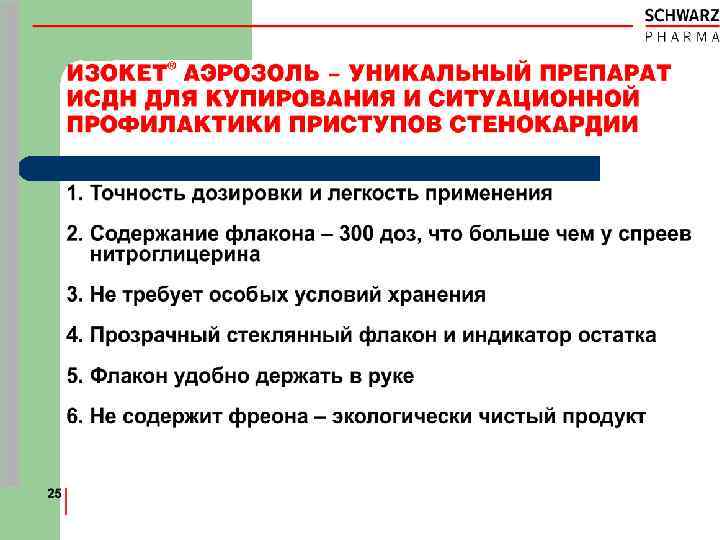

ИЗОКЕТ® l l -- Аэрозоль с насосом и дозатором (нет фреона) Прозрачный стеклянный флакон Индикатор маленького остатка Содержание флакона l 15 мл раствора l 375 мг ИСДН % l Пропиленгликоль l Этанол 89. 6 об. спрей